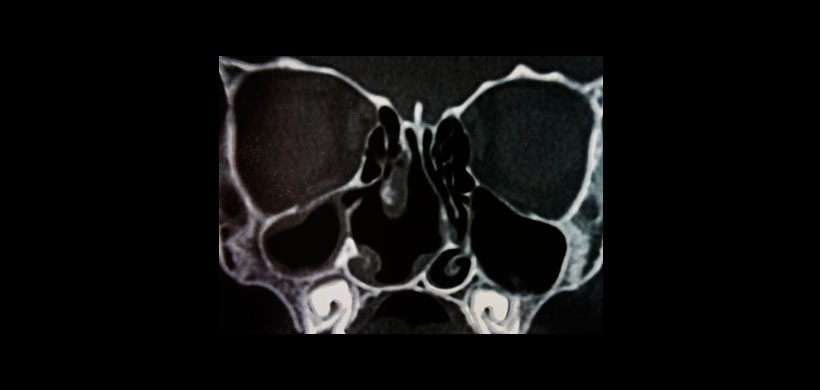

Finalmente el examen histopatológico dio como diagnostico final de mucocele sinusal, siendo realizada después de 2 meses una tomografía de control (Figura 2).

Figura 2: Tomografía de control después de 2 meses de la cirugía